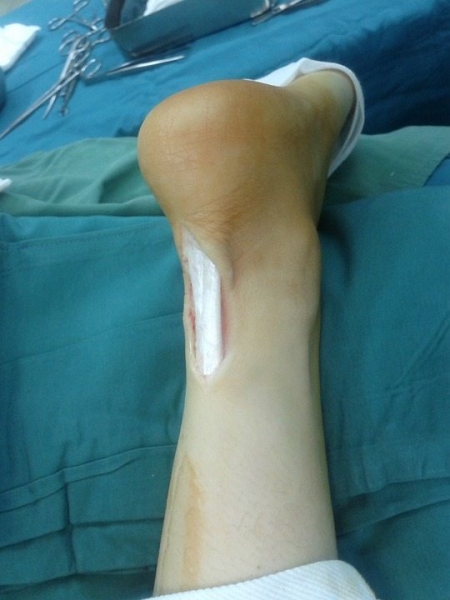

- Длина разреза не превышает нескольких сантиметров.

Общая длина разреза не превышает 3 см. Впоследствии шрам будет практически не заметен под нижнем бельем, при купании, пребывании на пляже.

При операции Мармара осуществляется небольшой разрез, который в дальнейшем будет практически незаметным